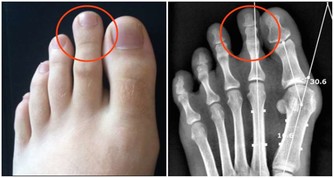

早上醒來腳落地感覺腳後跟痛,彷若針扎一般疼,稍微起身行走片刻緩解,但繼續運動或長久站立疼痛感又會襲來,此時應當提高警惕了,如果腳後跟並沒有紅腫且皮膚無破損,需要懷疑是足底筋膜炎的問題。